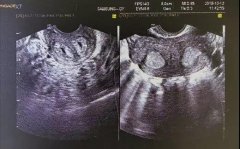

【新闻简介】先天性心脏病是一种常见的先天性发育畸形,也是导致流产、胎儿宫内死亡以及婴儿死亡的主要原因之一。 而胎儿心脏彩超是诊断胎儿有无先天性心脏病的首选影像学检查手段。孕妈妈..【详情】

【新闻简介】大家,知道吗? 胎儿最先发育的就是心血管 第2周开始,原始心管开始发育 60天左右,便可以听到TA的心声 真切的感受到一个新生命到来了 到17周,胎儿心脏发育几乎完成 一切......似乎..【详情】